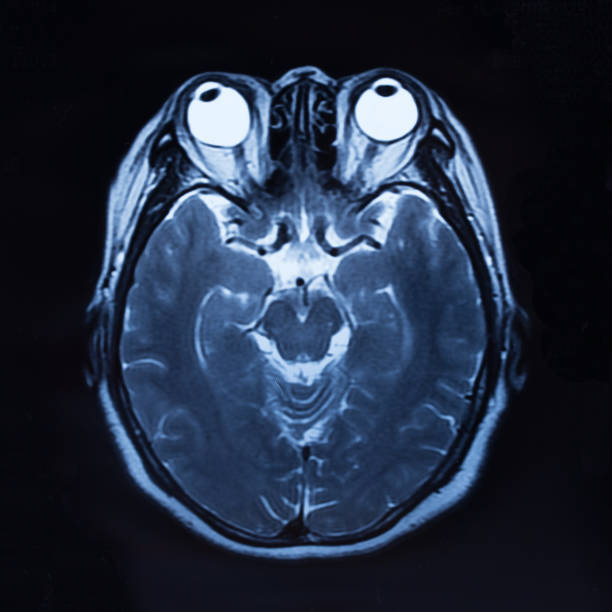

뇌졸중은 뇌경색, 뇌출혈 등 뇌 관련질환을 이르는 전체적인 질병을 나타내는 단어입니다. 개별적으로 살펴보면 뇌경색은 뇌혈관이 막히거나 다른 곳에서 색전물질이 혈관을 통해서 전달이 되어서 혈관이 막힐 때 나타나는 병이며 뇌출혈은 작은 혈관이 파열되어 뇌동맥류 같은 질병들이 있는 상태에서 높은 압력으로 파열되면서 뇌실질에 출혈이 일어나는 경우를 말합니다

따라서, 뇌에 혈액을 공급하는 뇌혈관에 문제가 발생하면 산소, 영양분이 뇌에 제때 제대로 공급 하지 못해 뇌조직과 뇌세포의 기능이 떨어지면서 여러가지 증상이 나타나 골든타임이 중요한 뇌졸중이기 때문에 위에서 언급했듯 전조증상을 미리 잘 알고 있는 것이 중요합니다.